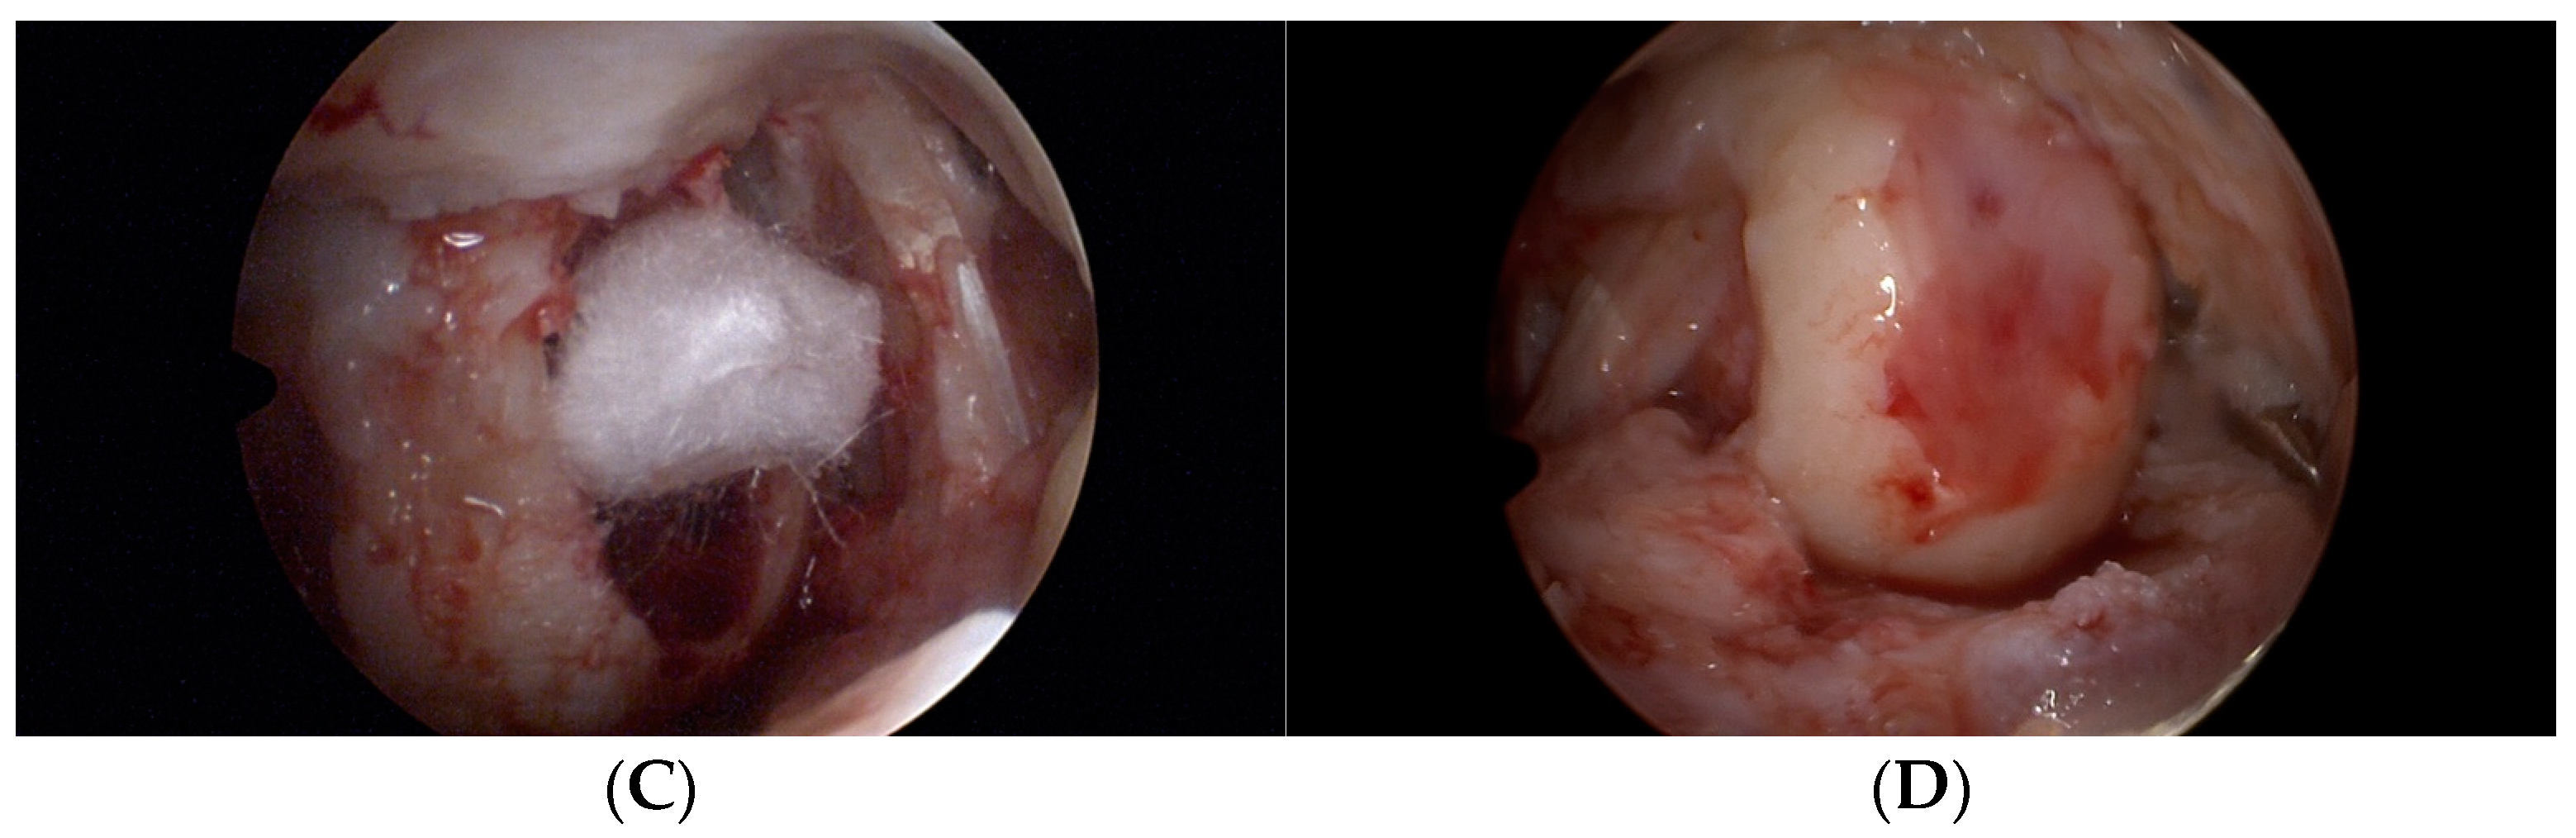

2.2. Operation Procedure